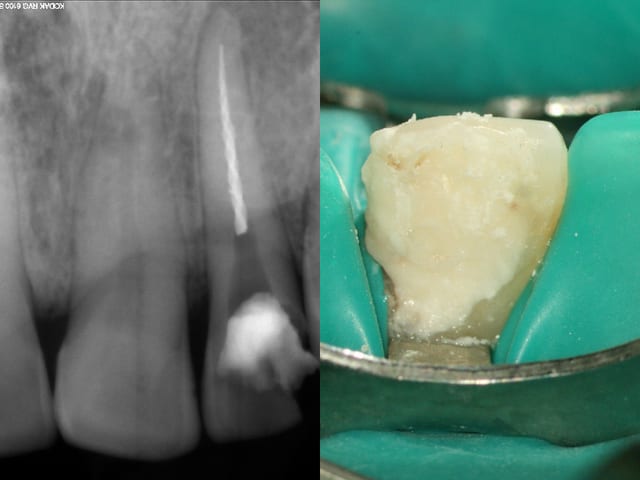

Ci joint un cas d'hier. Et je te le redis LDL, ce n'est aps 100%; ca ne marche pas à tous les coups...

Page2 d58xuk - Eugenol

Page4 vnzsfg - Eugenol

Page1 ujtadz - Eugenol

Page3 dyq9tu - Eugenol